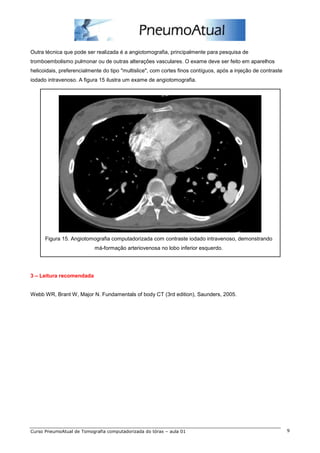

Outra técnica que pode ser realizada é a angiotomografia, principalmente para pesquisa de

tromboembolismo pulmonar ou de outras alterações vasculares. O exame deve ser feito em aparelhos

helicoidais, preferencialmente do tipo "multislice", com cortes finos contíguos, após a injeção de contraste

iodado intravenoso. A figura 15 ilustra um exame de angiotomografia.

Figura 15. Angiotomografia computadorizada com contraste iodado intravenoso, demonstrando

má-formação arteriovenosa no lobo inferior esquerdo.